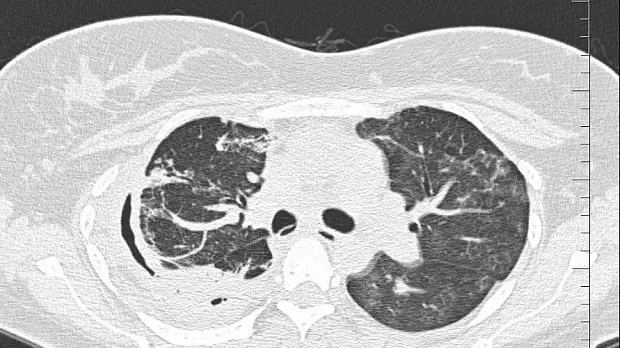

08.06.2020 проведена повторная установка блокатора в промежуточный бронх (блокатор Medlung №13) с хорошим клиническим эффектом (сброс воздуха по плевральному дренажу прекратился через 8 часов после вмешательства). Подтверждено данными Р-КТ органов грудной клетки.